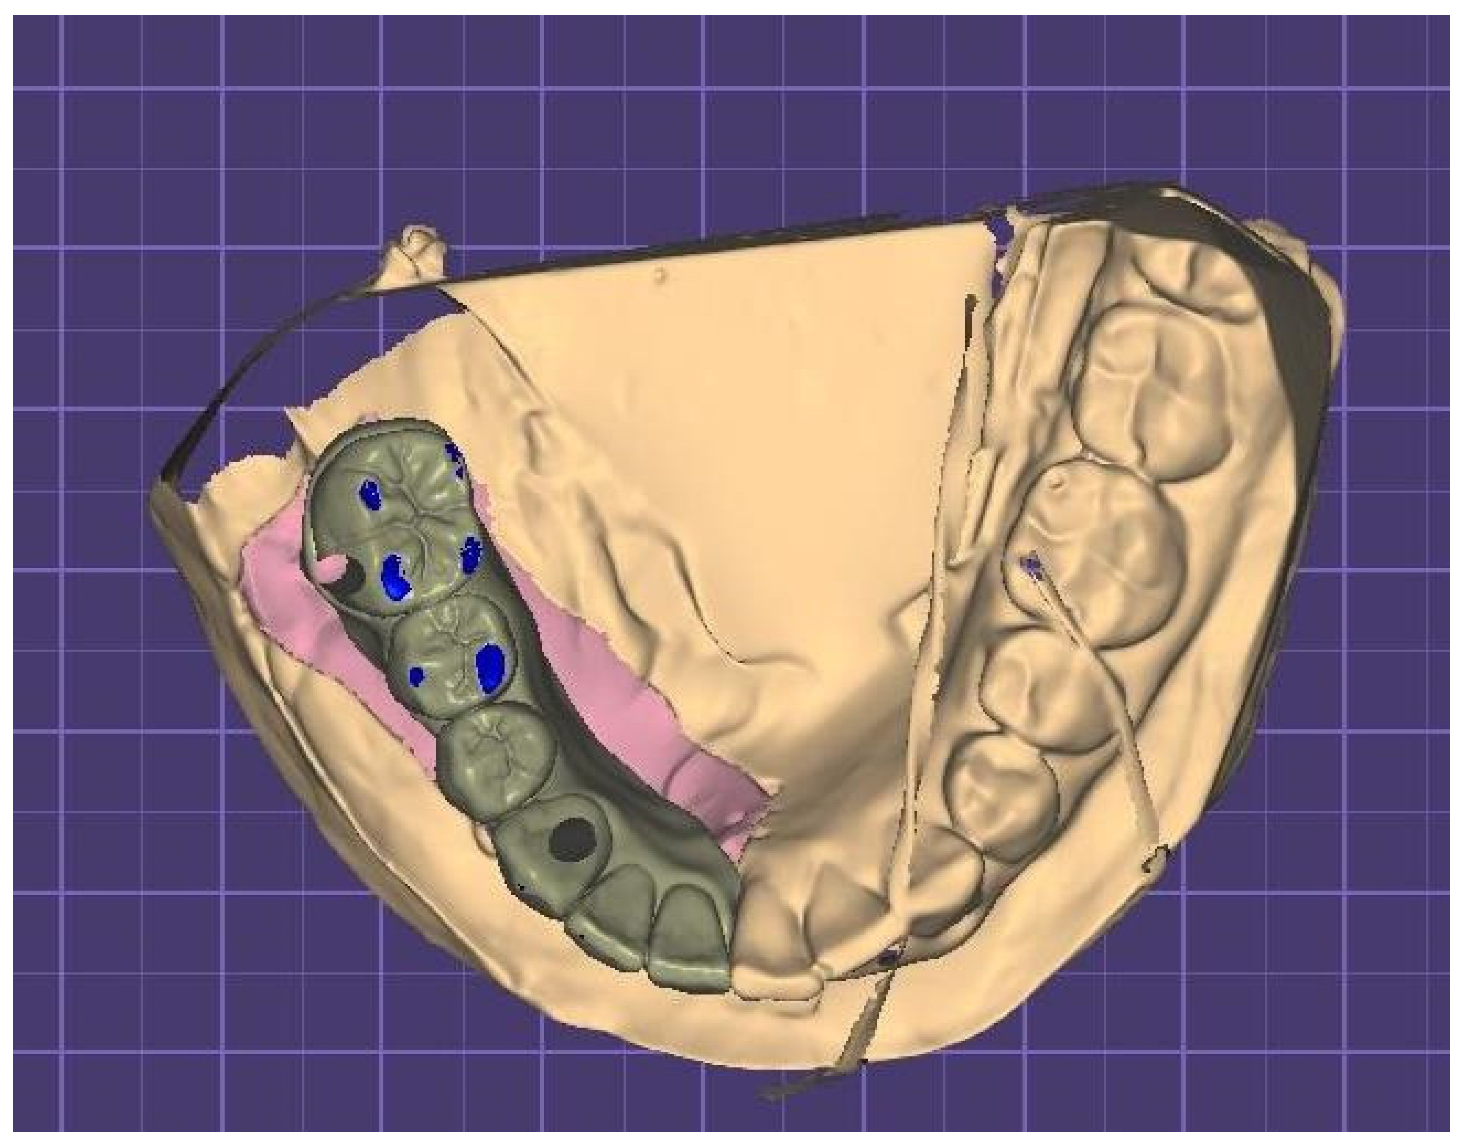

| 2022–2023 | Complementary exams and planification |

| 2023 | Surgery of 4 implants in the jaw |

| 2023–2024 | Start with rehabilitation phase |